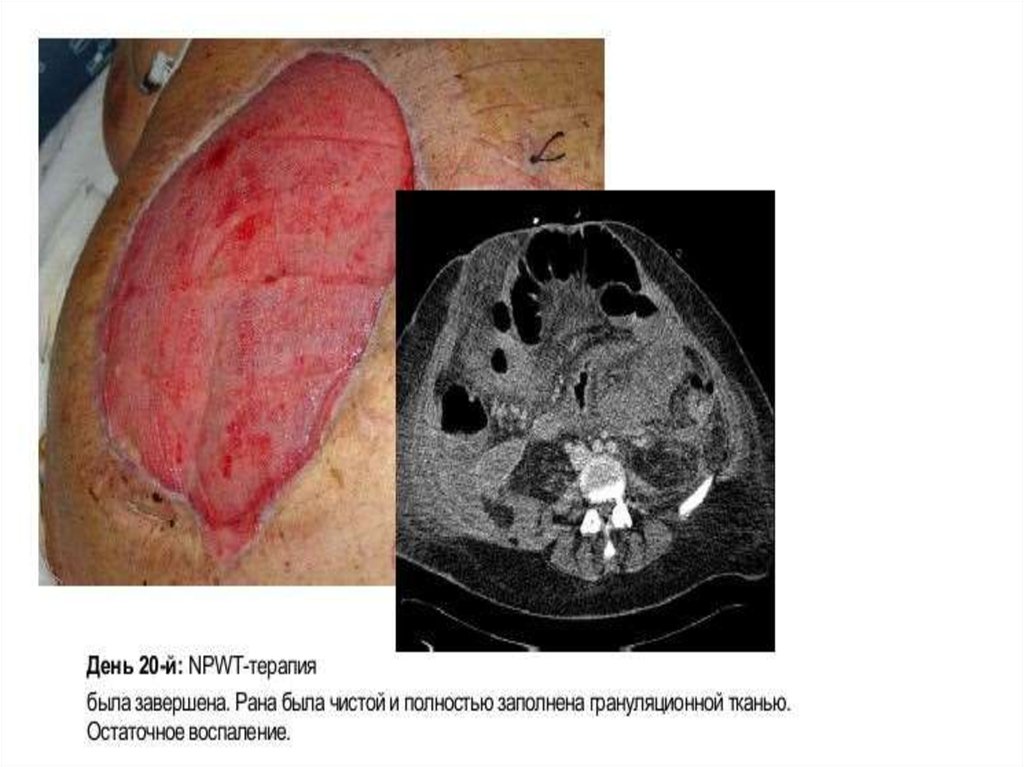

100. В клинике госпитальной хирургии вскрыт просвет псевдокисты поджелудочной железы, из ее просвета извлекаются эмболизирующие

агенты